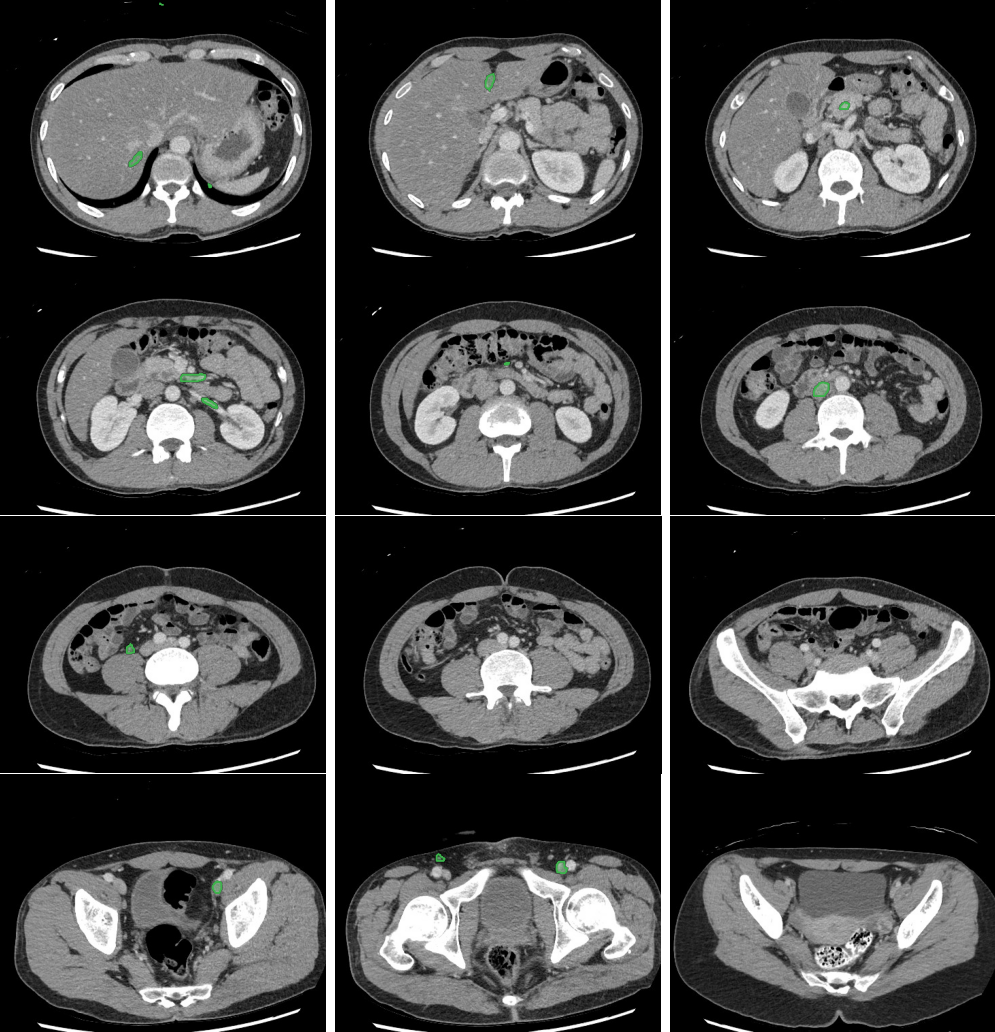

Slice 1

Slice 2

Slice 3

Slice 4

Slice 5

Slice 6

Slice 7

Slice 8

Slice 9

Slice 10

Slice 11

Slice 12